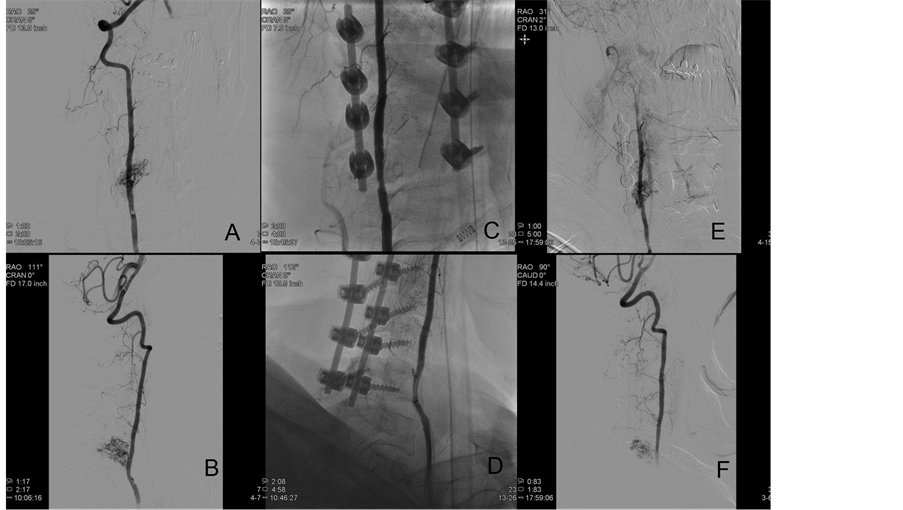

Treatment plan was started with a therapeutic spinal angiogram. The patient was placed under general anesthesia and neurophysiologic monitoring. A diagnostic angiogram was first performed showing a C5-C6 spinal vascular malformation fed by two arterial feeders from the right vertebral artery and, in a lesser extent, branches from the right thyro-cervical trunk. Selective micro-catheterization of the most superior feeder was achieved, and balloon-assisted embolization, to avoid reflux of the liquid agent into the vertebral artery, was performed using Onyx 18 (ev3, Irvine, California). The liquid material permeated well into the nidus and also occluded in a retrograde fashion the other vertebral feeder. Complete obliteration of the vertebral artery branches supply was achieved. However, when removing the microcatheter, Onyx stretched material was brought to the vertebral artery lumen, with mobile pediculated embolic material noticed in two angiographic runs. In order to prevent possible breakdown and potentially catastrophic vertebra-basilar artery emboli, an Enterprise self-expanding stent (Codman Neurovascular, Raynham, Massachusetts) was deployed to tackle the fragment against the vessel wall. Intraprocedural abciximab was given prior to stent deployment. No neuromonitoring changes were noted during the procedure, and the patient remained at his neurological baseline. Two months later, the angiogram was repeated showing patency of the vertebral artery stent, partial reopening of previous feeders and additional feeders from the right thyro-cervical trunk, specifically the right ascending cervical artery (Figure 3). This feeder was far more noticeable than in previous angiograms and could represent vascular recruitment from the spinal malformation. No further endovascular intervention was performed, and the decision was made to proceed with open targeted surgical decompression. Surgery was chosen over radiosurgery in order to achieve a faster clinical improvement and avoid possible nerve root radiation damage.

Figure 3. Angiographic views before Onyx embolization ((A) and (B)), immediately after embolization ((C) and (D)), and two months after the initial procedure ((E) and (F)). Significant reopening of the feeding vessels can be noticed coming from muscular branches of the right vertebral artery.